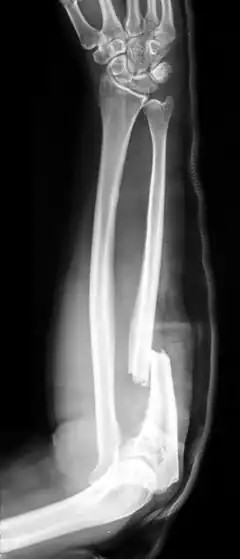

Fractures of the ulna can occur at different levels of the bone: near the wrist, in the middle or near the elbow.[2] The fracture may be confined to the ulna or accompanied with damage to the radius or the wrist or elbow joints.[2]

- Monteggia fracture - a fracture of the near to elbow end of the ulna with the dislocation of the head of the radius at the elbow joint.[2]